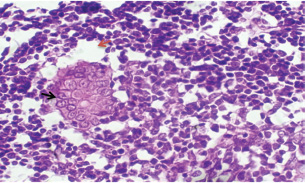

At 21 days post-infection, the lungs display moderate venous dilation and congestion, with abnormal leukocytes, indicating ongoing vascular compromise (Fig. 9). The liver showed necrotic changes in the fibrous capsule region, focal inflammatory cell infiltration, and intact hepatic cords, indicating sustained but localized damage (Fig. 10). The spleen exhibited plasma cell and macrophage proliferation within the red pulp, mild sinus dilation, and a few megakaryocytes, suggesting chronic immune activation (Fig. 11). The kidneys showed atrophic glomerular tufts and cystic dilation of adjacent tubules, indicating worsening renal pathology (Fig. 12). The mesenteric lymph nodes showed lymphoid follicles containing abnormal plasma cells and macrophages within the necrotic foci (Fig. 13).

Fig. 12. A histopathological section of the kidney (G2) at 21 days postinfection showing evidence of an atrophic tuft of many glomeruli recorded with cystic dilation of adjacent tubules (H&E stain X10).